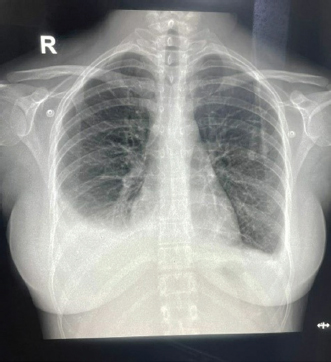

USG’s whole abdomen revealed hepatomegaly and mild to moderate ascites. In view of melena and thrombocytopenia, 6 units of random donor platelets were transfused. A workup for fever with thrombocytopenia and polyserositis was started. Dengue RTPCR, NS1 antigen, IgM, Weil felix, and VDRL were negative. Viral markers (HIV/HBsAg/Anti HCV/Anti HAV IgM/Anti HEV IgM) were negative. Scrub IgM, Brucella IgM, Urinary legionella antigen, CMV PCR, and Leptospira IgM were negative. Malaria Ag and P/S for the malaria parasite were negative. The widal test and Typhidot IgM were negative. CPK and CK-MB were negative. Stool occult blood (three samples) were negative. Covid PCR was negative. Blood and urine C/S were negative. Urine KOH revealed few budding yeast cells. Urine fungal culture was negative. Workup for EBV revealed 24,300 copies of EBV RTPCR and EBV IgM and IgG were positive. We did an autoimmune workup considering a young female with polyserositis but both ANA by Immunofluorescence and ANA profile were negative. Direct and indirect Coombs tests were negative. By the end of first week of admission, thrombocytopenia started improving but she had a persistent cough and fever although spikes were reduced. A 2D echo revealed trace pericardial effusion. Repeat Chest X-ray revealed persistent bilateral pleural effusion (Right > Left) (Fig. 2). In view of persistent effusion, we decided to perform a CECT chest and abdomen which revealed evidence of moderate right pleural effusion, minimal fluid in the left pleural cavity with atelectatic changes in the adjacent lung, oedematous thickened gallbladder and mild ascites (Figs. 3 and 4).

Fig. 4. CECT abdomen suggestive of edematous thickened gall bladder and mild ascites.